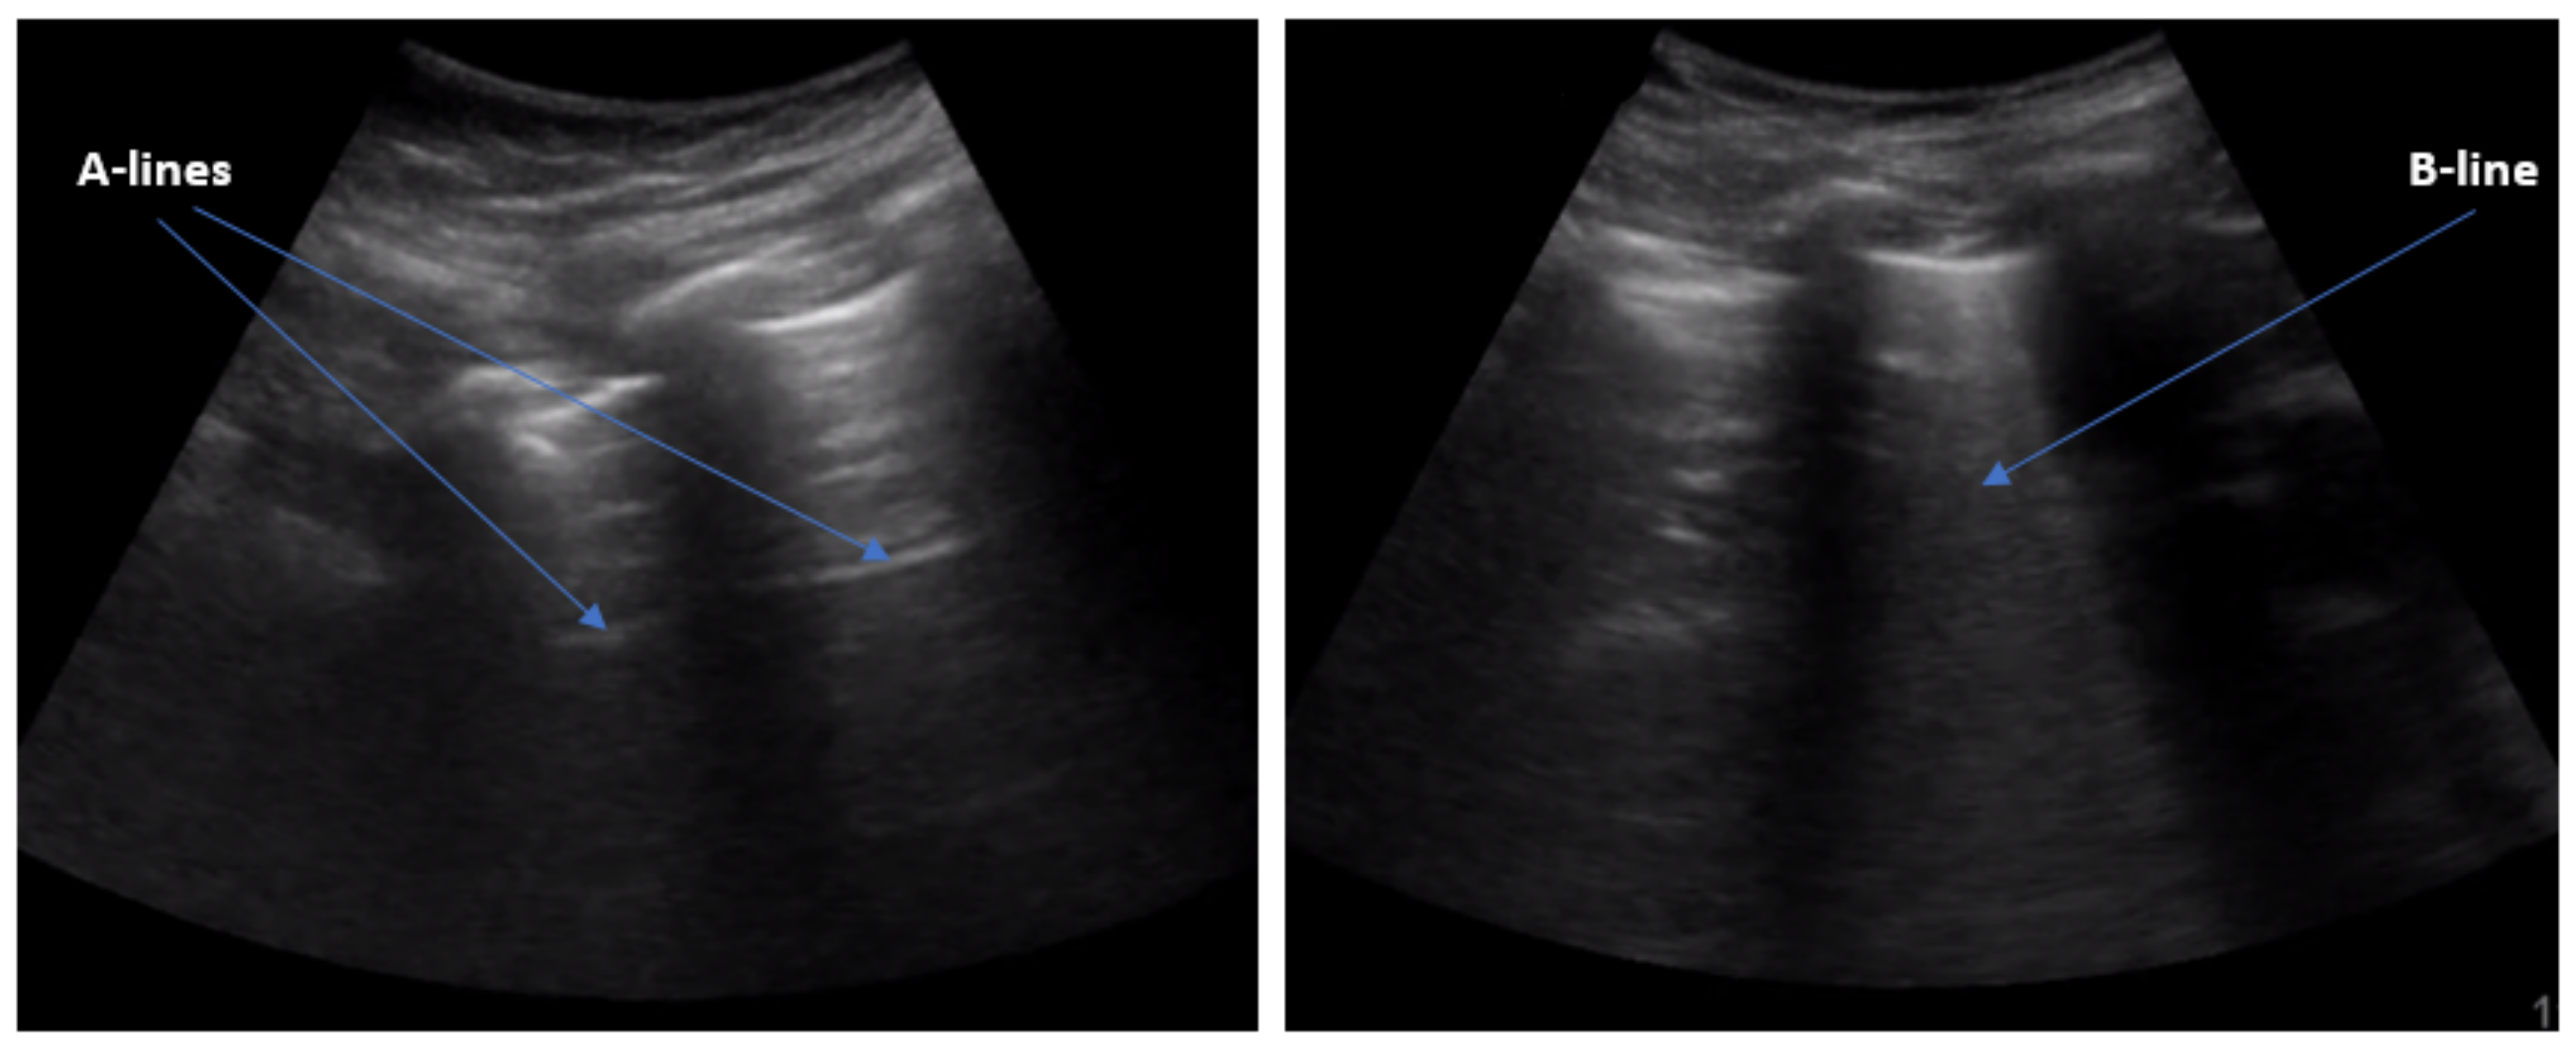

:1. Introduction

3.1. Convolutional Frame Feature Extraction Network

3.2. Spatial Attention Mechanism